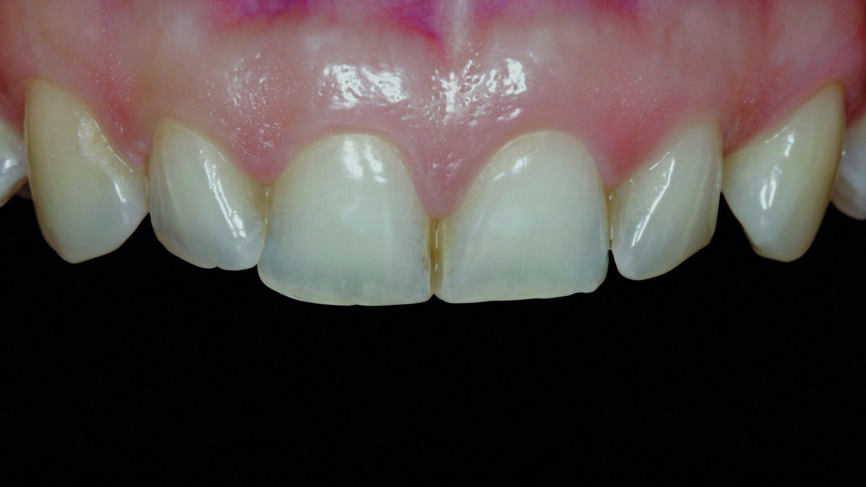

Une patiente âgée de 35 ans s‘est présentée au cabinet dentaire avec le souhait profond d‘un changement de l‘esthétique de la région antérieure (Fig. 1). Une maquette en cire diagnostique a été réalisée puis un mock-up en composite, afin d‘avoir une représentation préliminaire du résultat final.

Fig. 1 : Photographie initiale des dents antérieures avant le traitement orthodontique